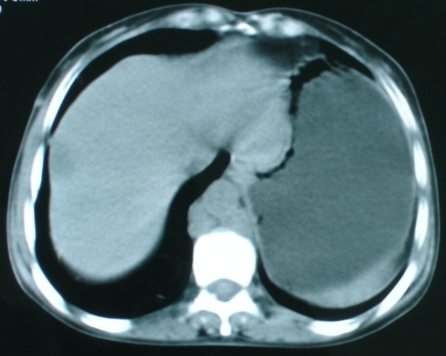

以下是引用zsl6918在2008-11-4 19:14:00的发言:[br]多发转移性改变,子宫改变不除外为原发灶